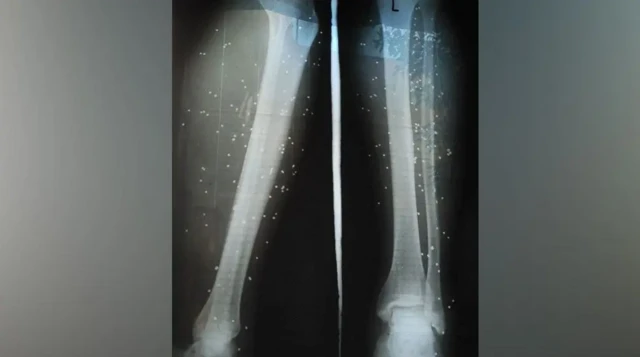

چند روز بعد یک جراح متخصص چند ساچمه را از بدنش خارج کرد. ولی به او گفت که: «اینها هم مثل ترکشهای زمان جنگ است، نمیشود درشان آورد و در بدن میماند.»

منبع تصویر، HRANA